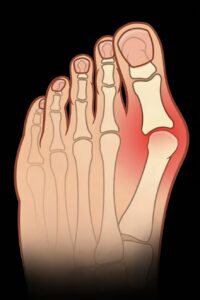

Es handelt sich um eine Funktionsbeeinträchtigung der Schultergelenksbeweglichkeit. Die Rotatorenmanschette des Schultergelenkes befindet sich in einem engen Sehnenkanal, der von dem knöchernen Eckgelenk (Acromion) und dem Oberarmkopf (Humerus) begrenzt wird. Die geschwollenen Sehnen reiben bei Bewegung in dem anatomisch engen Raum und somit kommt es zur Entzündung bzw. zu Schmerzen. Der akute Schulterschmerz tritt häufig bei jüngeren und aktiven Patienten auf. Leitsymptom ist ein dumpfer, ziehender Schmerz im Bereich des Muskulus deltoideus. Der Arm hängt in Schonhaltung vom Körper herab, Schulterbewegungen über 90° Grad sind kaum möglich. Der chronische Schulterschmerz führt zu Schonhaltung und Atrophie der schulterführenden Muskulatur.

Diagnostik: typischer Untersuchungsbefund mit Einschränkung der Schulterbeweglichkeit (“schmerzhafter Bogen“). Ultraschall (Sonographie), Röntgen zur Darstellung der knöchernen Strukturen oder Kalkdepots. Der „Goldstandard“ ist die Magnetresonanztomographie (MRT). Hiermit lassen sich Bänder, Sehnen, Schleimbeutel und insbesondere die Rotatorenmanschette darstellen.

Diagnostik: typischer Untersuchungsbefund mit Einschränkung der Schulterbeweglichkeit (“schmerzhafter Bogen“). Ultraschall (Sonographie), Röntgen zur Darstellung der knöchernen Strukturen oder Kalkdepots. Der „Goldstandard“ ist die Magnetresonanztomographie (MRT). Hiermit lassen sich Bänder, Sehnen, Schleimbeutel und insbesondere die Rotatorenmanschette darstellen.

Therapie: Krankengymnastik und Manuelle Therapie zur Stärkung der Schultermuskulatur und zum Erhalt der Beweglichkeit ist der wesentliche Bestandteil der Therapie. Im akuten Stadium ist meistens nur die gezielte Injektion mit einem entzündungshemmenden Schmerzmittel (Kortikoid) hilfreich. Die individuelle Beratung umfasst das Verhalten im Alltag, die körperliche Belastung in Beruf und Sport (Vermeidung von Überkopfarbeiten, Sportarten mit starker Beanspruchung der Schultern).

Prognose: Der Verlauf der Erkrankung ist meist günstig, schwere Verlaufsformen sind selten. Nur in vereinzelten Fällen ist eine Operation (Arthroskopie, ggf. Acromioplastik) notwendig.

Es handelt sich um eine schmerzhafte Entzündung eines Schleimbeutels (Bursa) in Kombination mit einer Abnutzung (Degeneration) von Sehnengewebe. Die Rotatorenmanschette des Schultergelenks befindet sich in einem engen Sehnenkanal, der vom knöchernen Eckgelenk (Acromion) und vom Oberarmkopf (Humerus) begrenzt wird. Die geschwollenen Sehnen reiben bei Bewegung in diesem anatomisch engen Raum, und es kommt zur Entzündung. Der akute Schulterschmerz tritt vorzugsweise bei jüngeren und aktiven Patienten auf. Leitsymptom ist ein dumpfer, ziehender Schmerz im Bereich des Muskulus deltoideus. Der Arm hängt in Schonhaltung vom Körper herab, Schulterbewegungen über 90° Grad sind kaum möglich. Der chronische Schulterschmerz führt zu Schonhaltung und Atrophie der schulterführenden Muskulatur.

Diagnostik: Typischer klinischer Untersuchungsbefund mit Einschränkung der Schulterbeweglichkeit („schmerzhafter Bogen”). Ultraschall (Sonographie) beider Schultern im Seitenvergleich, Röntgen zur Darstellung der knöchernen Strukturen oder Kalkdepots. Der „Goldstandard“ ist die Magnetresonanztomographie (MRT). Hiermit lassen sich die Muskeln, Bänder, Sehnen, Schleimbeutel und insbesondere die Rotatorenmanschette darstellen.

Diagnostik: Typischer klinischer Untersuchungsbefund mit Einschränkung der Schulterbeweglichkeit („schmerzhafter Bogen”). Ultraschall (Sonographie) beider Schultern im Seitenvergleich, Röntgen zur Darstellung der knöchernen Strukturen oder Kalkdepots. Der „Goldstandard“ ist die Magnetresonanztomographie (MRT). Hiermit lassen sich die Muskeln, Bänder, Sehnen, Schleimbeutel und insbesondere die Rotatorenmanschette darstellen.

Therapie: Krankengymnastik und Manuelle Therapie zur Stärkung der Schultermuskulatur und zum Erhalt der Beweglichkeit ist der wesentliche Bestandteil der Therapie. Im akuten Stadium ist meist nur die gezielte Injektion mit einem entzündungshemmenden Schmerzmittel hilfreich. Weitere Maßnahmen sind Elektrotherapie, TENS oder auch Akupunktur. Die individuelle Beratung umfasst das Verhalten im Alltag, die körperliche Belastung in Beruf und Sport (Vermeiden von Überkopfarbeiten und von Sportarten mit starker Beanspruchung der Schultern). Die Extrakorporale Stoßwellentherapie (ESWT) hat sich in den letzten Jahren zu einer neuen wegweisenden Therapieform in der Orthopädie entwickelt. Stoßwellen sind akustische Schallwellen, die gezielt in einem Brennpunkt (Fokus) gebündelt werden und dort ihre Wirkung entfalten. Mit Hilfe der Stoßwellentherapie wird die Aktivität der Schmerzfasern reduziert, die Durchblutung angeregt und Entzündungen und Reizungen vermindert. Dies führt zur schnellen Linderung der Beschwerden und zur Heilung. Neben ihrer mechanischen Kraft, die zur Therapie eingesetzt wird, sind keine Nebenwirkungen bekannt.

Prognose: Der Verlauf der Erkrankung ist meist günstig, schwere Verlaufsformen sind selten. Nur in vereinzelten Fällen ist eine Operation notwendig(Arthroskopie, ggf. Acromioplastik).